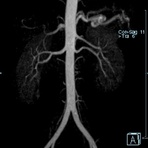

- Bauchgefäße

- Erfassung und Verlaufskontrolle bei arteriellen Aneurysmen (Aussackungen der Arterien), vor allem der Bauchaorta

- Darstellung von Gefäßengen an Nierenarterien, Baucharterien und Becken-/Beinarterien

- MR-Angiographie mit Kontrastmittel

- Erfassung arterieller und venöser Gefäße/Bypässe aller Körperregionen mit 3D-Rekonstruktion

- je nach klinischer Fragestellung zeitaufgelöste MR-Angiographie (4D-MRA) z.B. bei Frage arteriovenöse Fistel/ Shunt oder Darstellung Unterschenkelarterien vor geplanter Bypassoperation.